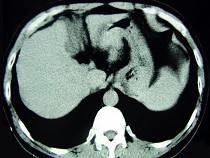

问题 男,52岁,中上腹痛,影像检查如图,最可能的诊断是 ( )

选项 A.慢性肥厚性胃炎 B.胃癌 C.胃溃疡 D.胃平滑肌瘤 E.胃平滑肌肉瘤

答案 D